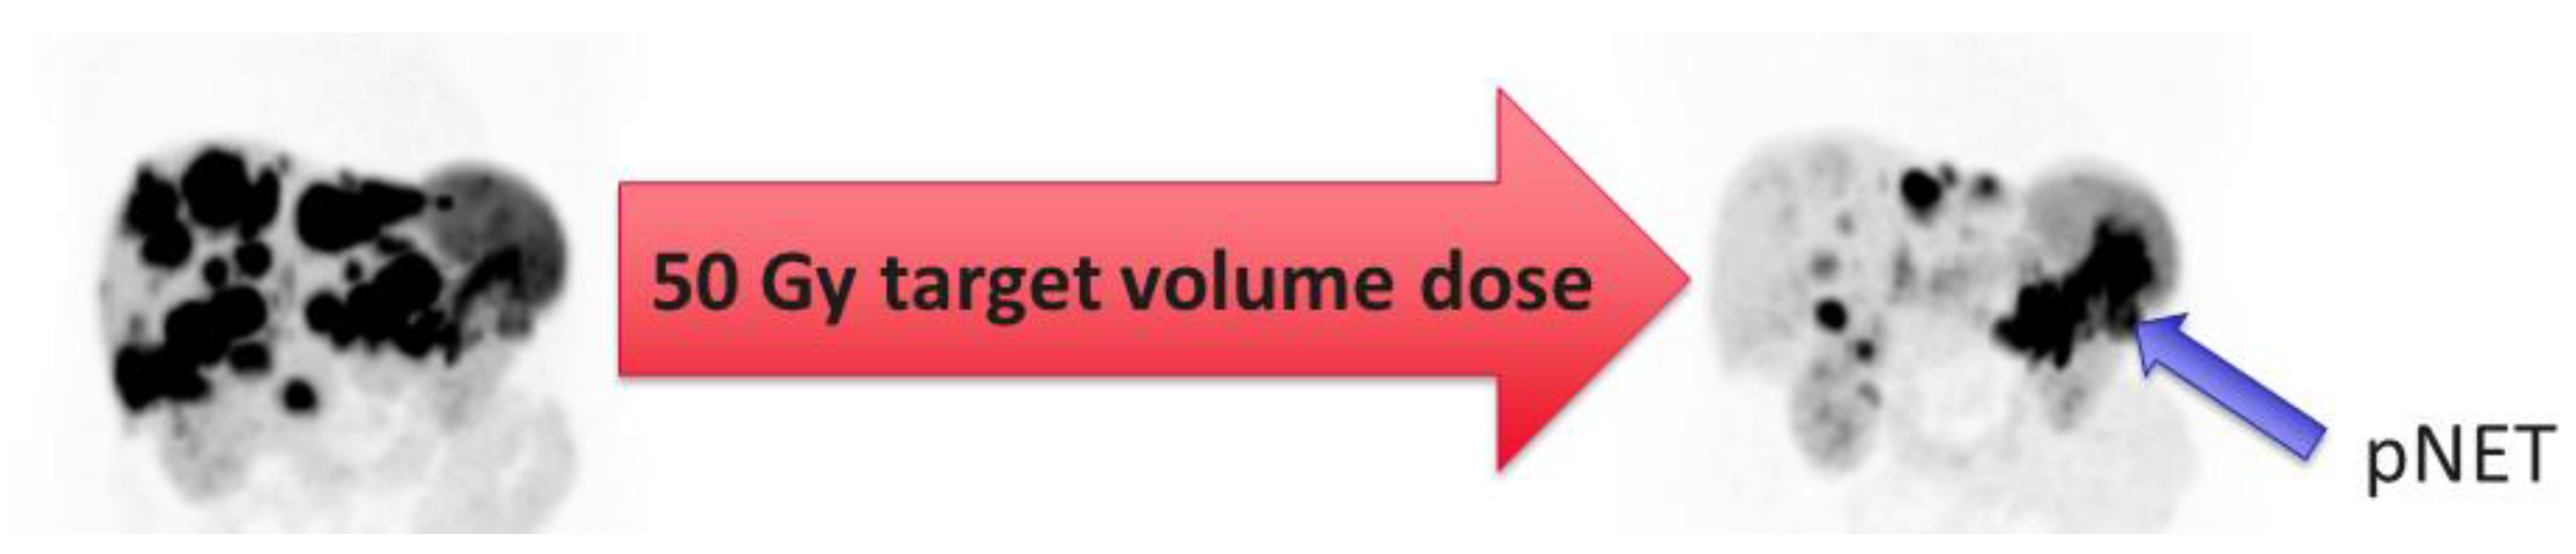

2. How Is Radioembolization Performed?

- Ebbers, S.C.; van Roekel, C.; Braat, M.N.G.J.A.; Barentsz, M.W.; Lam, M.G.E.H.; Braat, A.J.A.T. Dose-response relationship after yttrium-90-radioembolization with glass microspheres in patients with neuroendocrine tumor liver metastases. Eur. J. Nucl. Med. Mol. Imaging 2022, 49, 1700–1710. [Google Scholar] [CrossRef]